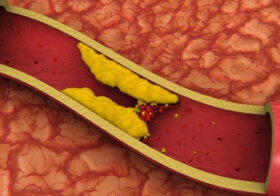

오늘, 이 글에서는 고콜레스테롤을 조절하는 자연적인 방법을 주제로 살펴볼 것이다. 콜레스테롤은 지방의 일종으로 지질이라고 부르기도 한다. 보통 몸에서 자연적으로 형성되고…